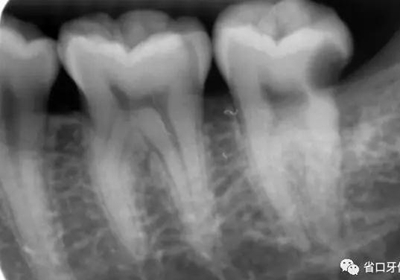

圖2 術(shù)前X片示遠(yuǎn)中鄰面牙體低密度影累及髓角